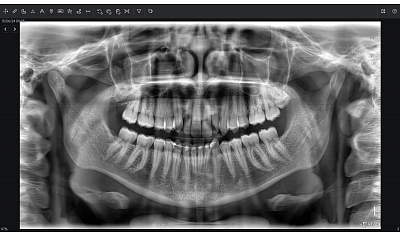

Diagnostinės galimybės

2D vaizdai

- Panoraminiai (PAN) vaizdai su keliais fokusavimo sluoksniais

- Cefalometriniai vaizdai (jei komplektacija su CEPH arm)

- Detalios žandikaulių sričių projekcijos

- Direct Conversion sensorius – aukštos kokybės SuperHD 2D vaizdai net mažoje dozėje

- MultiPAN funkcija – kelios fokusavimo zonos vienu panoraminiu skenu

- SuperHD vaizdai: aukšta vaizdo kokybė 2D ir 3D režimuose net esant mažai dozei